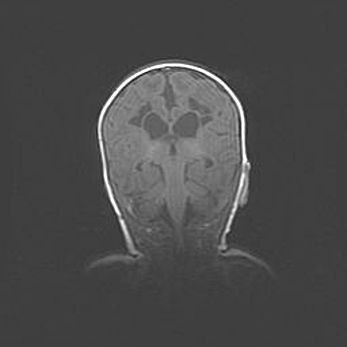

Сообщающаяся гидроцефалия. Кистозная энцефаломаляция головного мозга.

Возраст: 3 месяца 4 дня

Вес: 3100 г

Пол: женский

Окружность головы: 34 см

Срок гестации: 31 неделя

Кистозная энцефаломаляция головного мозга - одна из форм поражения головного мозга в детском возрасте. Характеризуется возникновением множественных и распространённых кист в коре, белом веществе и подкорковых образованиях головного мозга у плодов, новорождённых и детей раннего возраста. Развитие кистозной энцефаломаляции связано с внутриутробной асфиксией и гипотонией, родовой травмой, тромбозом синусов, пороками развития сосудов, инфекциями, сепсисом и другими причинами. Наиболее значимые инфекционные агенты: вирусы простого герпеса, цитомегалии, краснухи, токсоплазмы, энтеробактерии, золотистый стафилококк и другие.